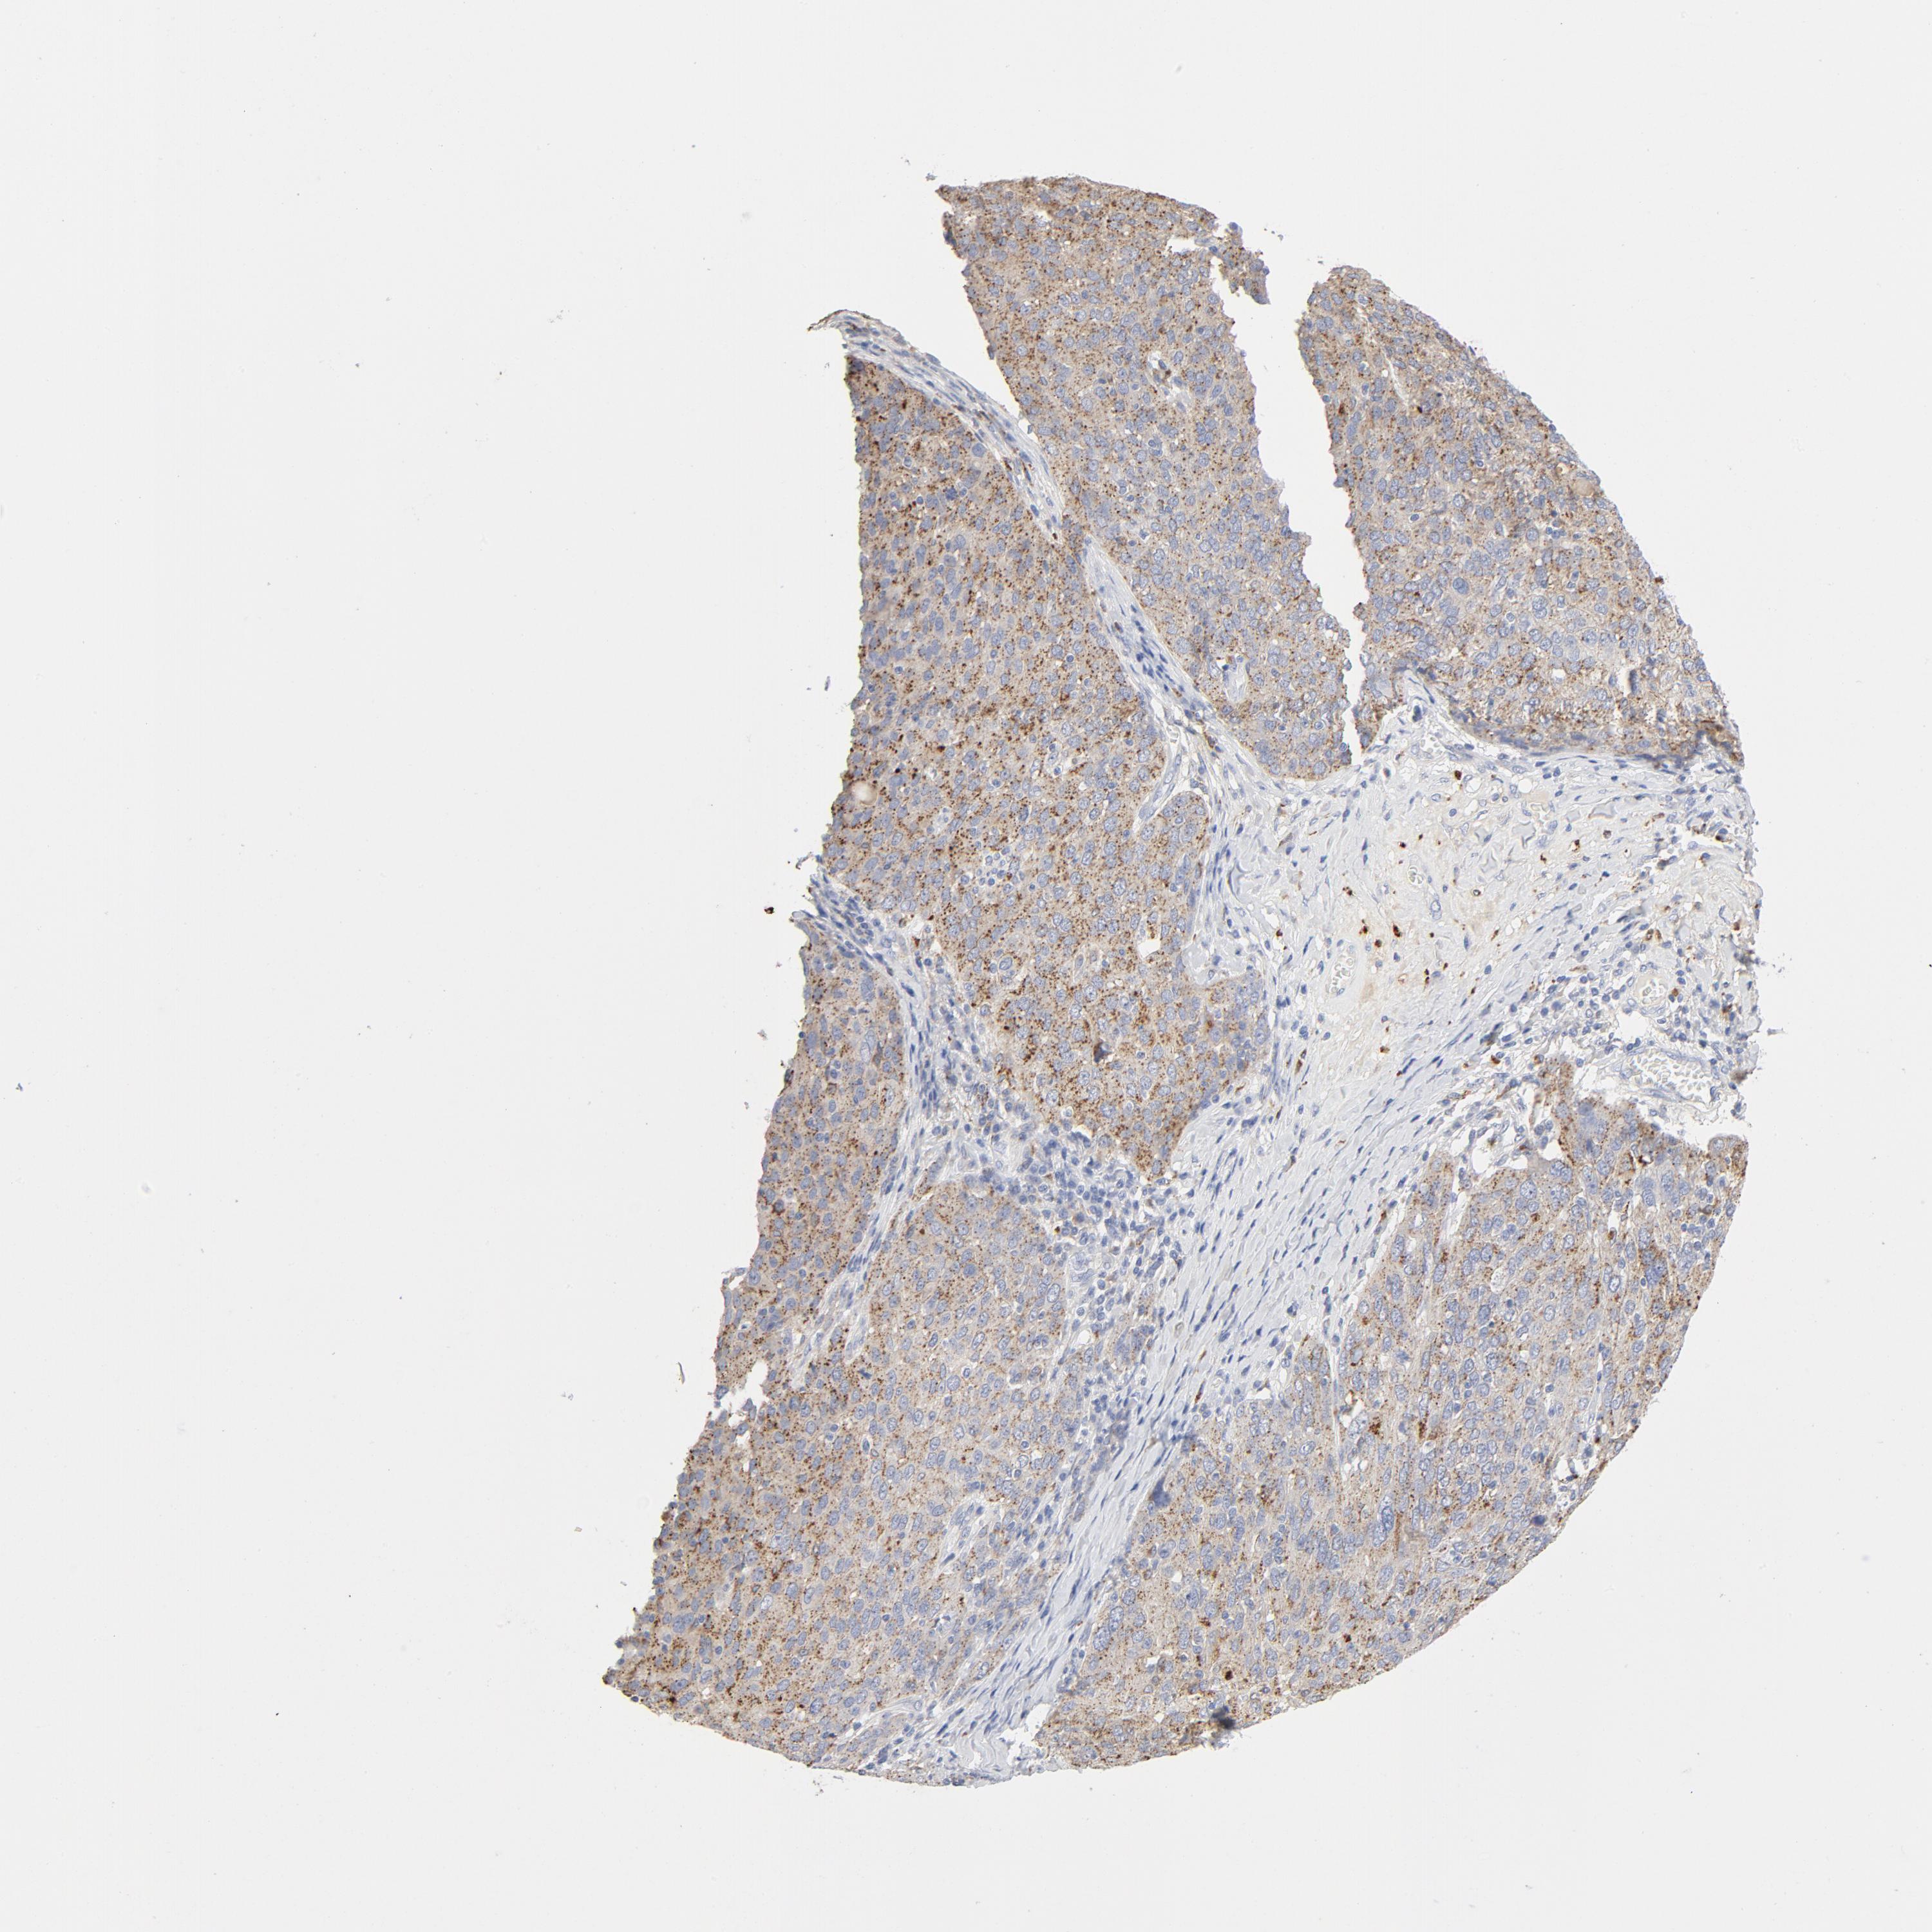

OVARIAN CANCER - Protein expressioni

A mouse-over function shows sample information and annotation data. Click on an image to view it in a full screen mode. Samples can be filtered based on level of antibody staining by selecting one or several of the following categories: high, medium, low and not detected. The assay and annotation is described here.

Note that samples used for immunohistochemistry by the Human Protein Atlas do not correspond to samples in the TCGA dataset.

Antibody stainingi

Antibody staining in the annotated cell types in the current human tissue is reported as not detected, low, medium, or high, based on conventional immunohistochemistry profiling in selected tissues. This score is based on the combination of the staining intensity and fraction of stained cells.

Each image is clickable and will lead to virtual microscopy that enables deeper exploration of all samples and also displays staining intensity scores, fraction scores and subcellular localization as well as patient and tissue information for each sample.

Antibody HPA003756

Staining

High

Medium

Low

Not detected

Intensity

Strong

Moderate

Weak

Negative

Quantity

>75%

75%-25%

<25%

None

Location

Nuclear

Cytoplasmic/membranous

Cytoplasmic/membranous,nuclear

Cystadenocarcinoma, serous, NOS

Cystadenocarcinoma, mucinous, NOS

Carcinoma, endometroid